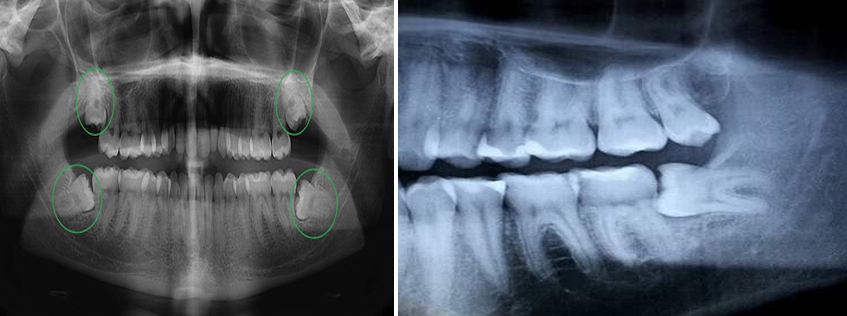

Hình ảnh X-quang răng số 8 mọc lệch